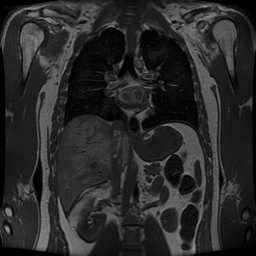

We evaluate the proposed methodology on three different images: the Shepp–Logan phantom, a human head, and a human abdomen. The human images were taken from the public dataset of the National Library of Medicine, as reported in Ref. [20]. These three images are shown in Fig. 4.

In Figures 5, 7, and 9, we present the sinograms, and in Figures 6, 8, and 10 the corresponding tomographic reconstructions of the Shepp–Logan phantom, a human head, and a human abdomen, respectively. Each figure shows results obtained from: (i) sparse projections using only the training samples, (ii) interpolation of the projections with the proposed methodology, (iii) interpolation of the projections with a feed-forward neural network, and (iv) interpolation of the projections with cubic spline interpolation. Columns (left to right) correspond to cases (i)–(iv), while rows (top to bottom) correspond to reconstructions obtained with 50, 100, and 150 training samples, respectively.

In addition, Tables 2, 3, and 4 report the squared error, computed as the Frobenius norm of the difference between the original image and the reconstructed approximations. This error provides a quantitative measure of the reconstruction quality for the Shepp–Logan phantom, the human head, and the human abdomen. The results show that the Learned column, corresponding to the proposed methodology, consistently achieves a lower mean squared error (MSE) than the reconstructions obtained from sparse training data, the feed-forward neural network (FNN), and cubic spline interpolation. This confirms that the proposed methodology outperforms the other approaches. The visual comparisons in Figures 6, 8, and 10 further support this conclusion, as the reconstructions in the middle column (proposed method) exhibit higher visual quality. Overall, these results demonstrate the superior performance of the proposed methodology in tomographic image reconstruction, without requiring any a priori knowledge of the sparse dataset.